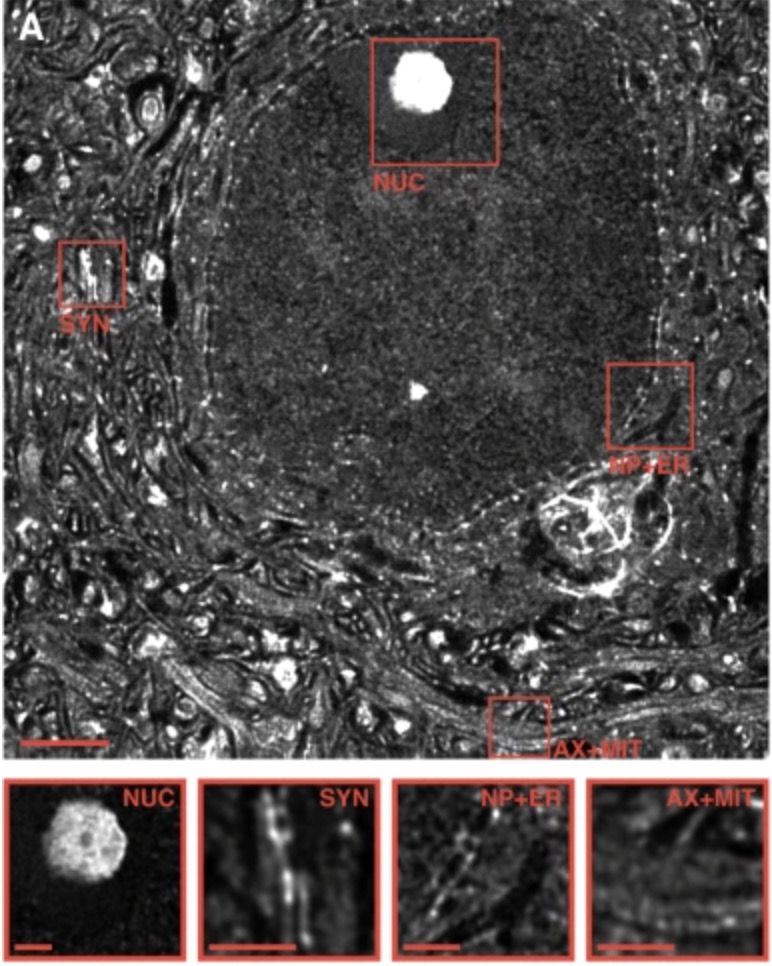

📚 New paper alert! 🎉 We are excited to announce the new publication in Acta Neuropathologica! 🧠🔬 This collaborative effort with the group of Chris Henstridge (University of Dundee ) has led to groundbreaking discoveries in the field of ALS research. link.springer.com/article/10.100…